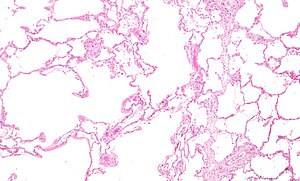

Emphysematous changes. H&E stain. | |

Microscopic

Features:[5]

- Large alveoli.

- Thin septa (no interstitial thickening).